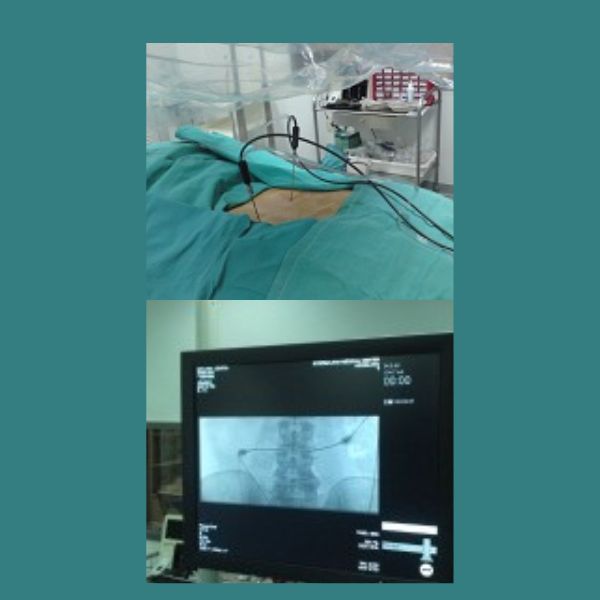

Οι βελόνες και τα ηλεκτρόδια τοποθετούνται στο δίσκο με ακτινοσκοπική καθοδήγηση και με αυστηρά άσηπτη τεχνική, για την αποφυγή του κινδύνου πρόκλησης δισκίτιδας (λοίμωξη του δίσκου). Μόλις ολοκληρωθεί η τοποθέτηση των ηλεκτροδίων και επιβεβαιωθεί η σωστή θέση τους με λήψη ακτινοσκοπικών εικόνων σε προσθιοπίσθια και πλάγια προβολή, ξεκινά η θεραπεία με τη ραδιοσυχνότητα η οποία διαρκεί ακριβώς 15 λεπτά της ώρας.